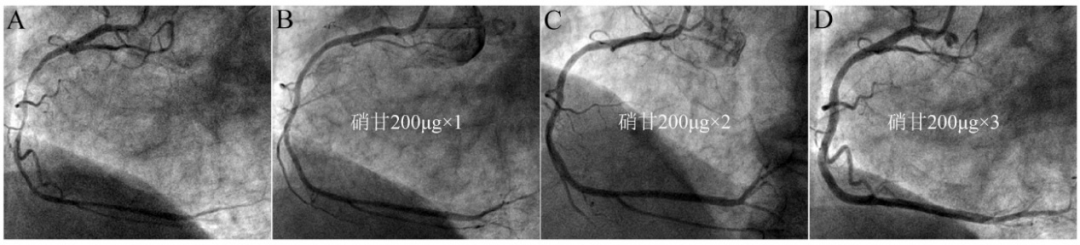

图12 导管深插诱发顽固性痉挛。

JR4造影导管深插至右冠(A),退至开口造影提示近段严重狭窄(B),冠脉内注射硝酸甘油200μg×3次只有部分缓解(C),继续推注200μg×2次后基本缓解(D)。说明部分患者强刺激后痉挛比较持久。该病人并无血管痉挛的临床表现,术后不需要抗痉挛治疗。